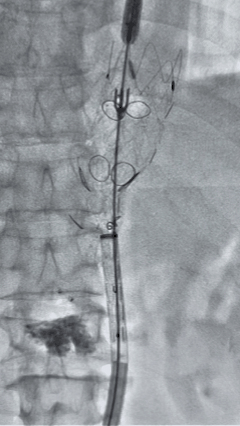

3. 经右股动脉导入超硬导丝,然后导入九州ku酷游G-Branch 胸腹主动脉主体覆膜支架TAAA3418120e7i1010 一枚,释放主体支架至内分支打开,然后经左侧肱动脉入路,抓捕预置导丝成功后,将长鞘进入内分支出口处。

4. 经长鞘导入导管后,超选入腹腔干动脉,送入九州ku酷游覆膜支架10*80mm一枚,近端重叠内分支,远端重叠腹腔干动脉,并予以10mm球囊后扩,手推造影显影良好。

5. 撤出腹腔干导丝导管,经左肱动脉长鞘继续抓捕预置导丝将长鞘超选至另一侧内分支,后超选进肠系膜上动脉,沿导丝送入九州ku酷游覆膜支架10*100mm一枚,近端重叠内分支,远端重叠于肠系膜上动脉,并予以10mm球囊后扩,手推造影显影良好。

6. 解除束径,打开近端后释放,经肱动脉长鞘超选支架外分支,并进一步超选右侧肾动脉,交换加硬导丝,送入覆膜支架6*50mm和7*60mm各一枚,并予以球囊后扩张,手推造影显影良好。

7. 经长鞘重新选入左侧外分支,并超选进左肾动脉,沿导丝送入外周血管覆膜支架7*60mm一枚,并予以球囊后扩张,手推造影显影良好。